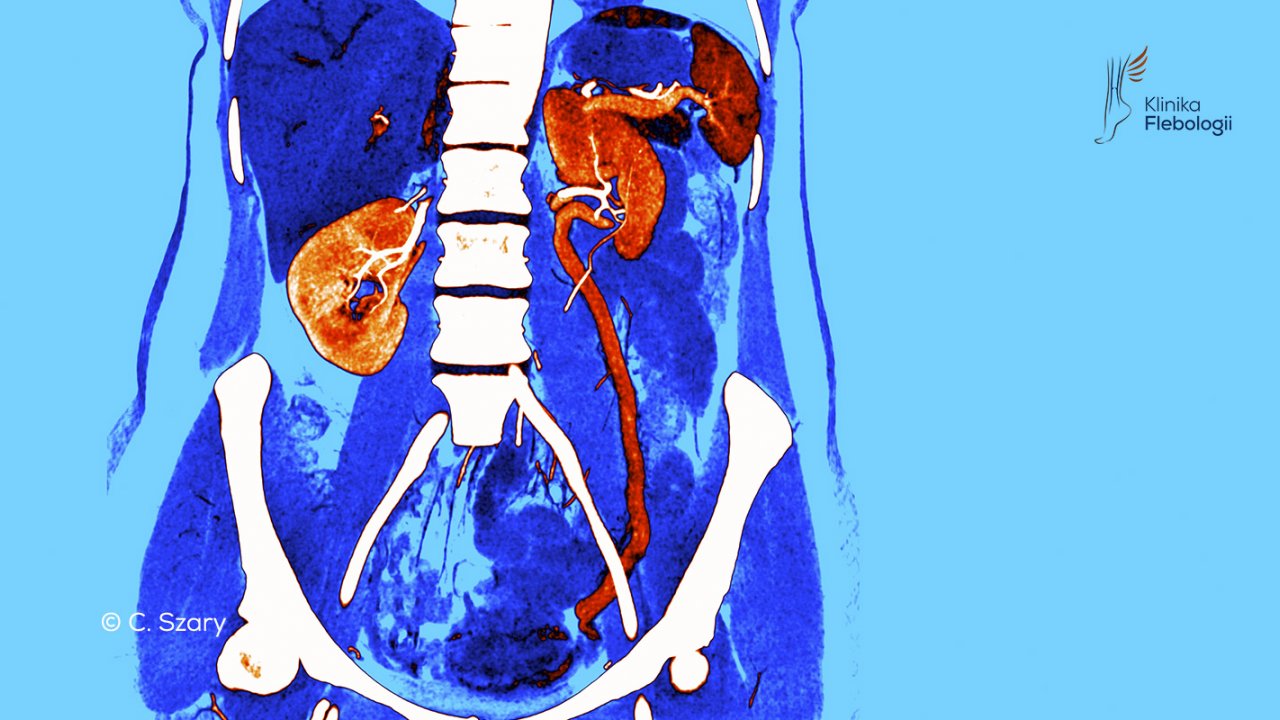

Wenografia tomografii komputerowej (CTV) to z kolei badanie o niebywałej precyzji anatomicznej. Dzięki nowoczesnej technologii jesteśmy w stanie obrazować układ żylny w bardzo szerokim zakresie. Rutynowo wykonujemy badania angio-TK w fazie żylnej kończynowej, obejmując obrazowaniem całą żyłę główną dolną, żyły biodrowe, udowe i naczynia żylne podudzi. Jest to wyjątkowe badanie, które pozwala nam jednocześnie wykluczyć incydent zakrzepowo-zatorowy i jednocześnie zobrazować układ żylny w obrębie kończyn dolnych.

Wenografia lewej żyły jajnikowej

Anomalia spływu poszerzonej lewej żyły jajnikowej w wenografii TK